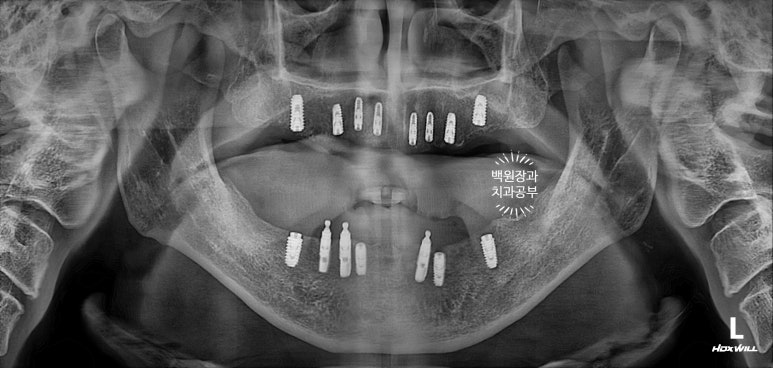

완성 후 치과용 파노라마 사진을 찍었습니다.

저희 치과에서 사용하는 오스템임플란트 네비게이션 시스템을 통해 임플란트 위치를 잘 계획하였고, 그 덕분에 각 치아의 가운데에 잘 맞춰져 임플란트가 위치된 것을 보실 수 있어요.

대부분의 환자분들이 전체임플란트 치료를 받으시면, 위턱 아래턱 각각 3덩어리의 보철물로 제작해드립니다.

즉, 어금니-앞니-어금니 총 3피스의 보철물로 나누어 제작하게 되는데 이는 향후 임플란트 수리도 용이하다는 큰 장점을 갖고 있죠.

옛날부터 임플란트 틀니용으로 사용하시던 임플란트 3개는 임플란트 주위염이 조금 있어 약~간 쇠기둥 색깔이 보인다는 단점이 있긴 하지만, 다른 임플란트들은 꽤나 예쁘게 제작이 되었네요.

위 아래 교합면 사진을 보시면, 과연 이게 임플란트인가? 싶으실거에요. 치아에 지르코니아 크라운을 붙인 것과 큰 차이를 못느낄 정도로 정말 자기 치아같이 예쁘게 제작된 임플란트 크라운을 보실 수 있습니다!!